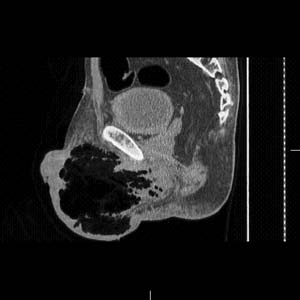

細菌培養 診斷主要依據臨床表現、傷口分泌物檢查和X線檢查,如損傷或手術後,傷口出現不尋常的疼痛,局部腫脹迅速加劇,傷口周圍皮膚有捻發音,並有嚴重的全身中毒症狀,如脈搏加速、煩躁不安進行性貧血,即應考慮有氣性壞疽的可能;傷口內的分泌物塗片檢查有大量革蘭染色陽性桿菌,X線檢查傷口肌群間有氣體,是診斷氣性壞疽的三個重要依據。